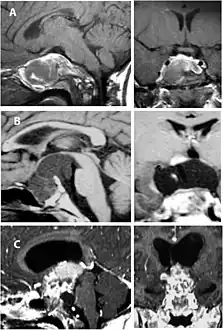

A physician can conduct a few scans and tests to diagnose a person with craniopharyngioma.[19] High-resolution magnetic resonance imaging (MRI) is commonly used as a diagnostic tool; however, computer tomography (CT) remains the gold standard imaging choice for craniopharyngioma diagnosis as it can detect the severity of the calcification within the tumour.[20]

In some cases, a powerful 3T (Tesla) MRI scanner can help define the location of critical brain structures affected by the tumor. The histologic pattern consists of nesting of squamous epithelium bordered by radially arranged cells. It is frequently accompanied by calcium deposition and may have a microscopic papillary architecture. A computed tomography (CT) scan is also a good diagnostic tool, as it detects calcification in the tumor.[21]

Enhanced T1 weighted MRIs of craniopharyngiomas